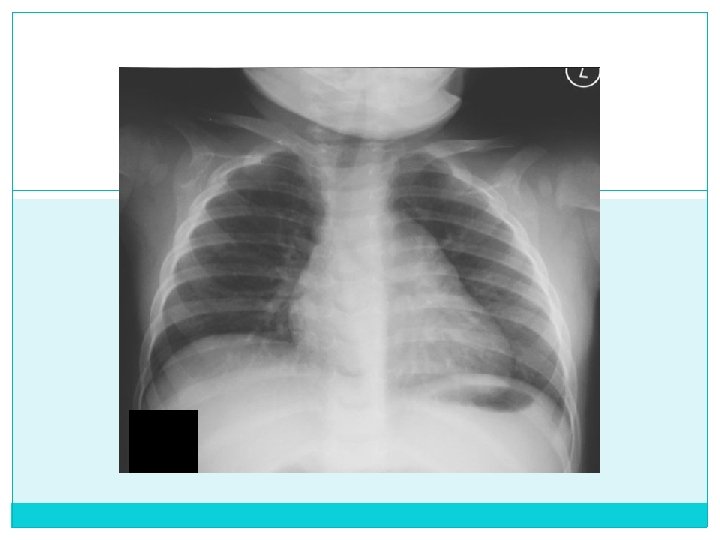

Caso número 2 Paciente de 8 años de edad con cuadro de 16 dias de tos seca de predominio nocturno, no asociado a otra sintomatología Niega antecedentes patológicos Examen físico es normal